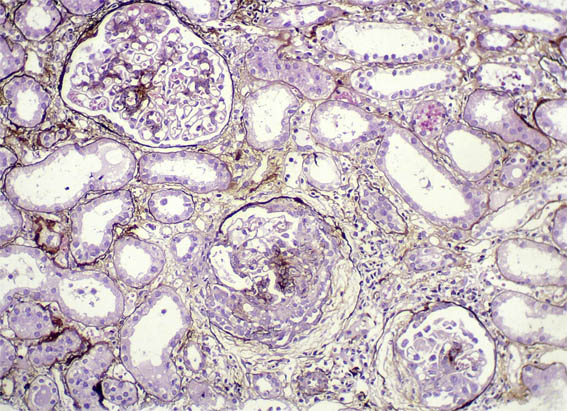

Figure 9. Methenamine-silver stain, X200.